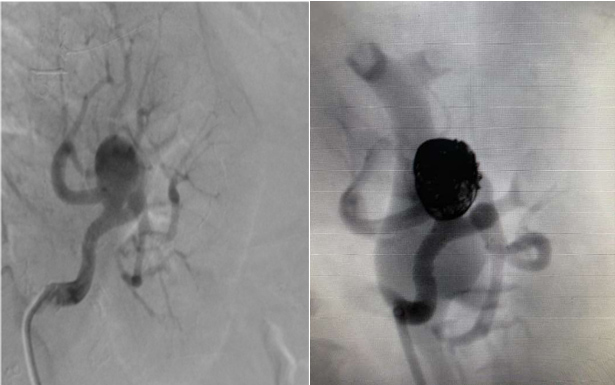

Caso realizado pelo serviço HCI da Santa Casa de Ribeirão Preto, evidenciando um grande aneurisma na artéria renal esquerda que foi tratado com técnica endovascular sendo utilizado coils e stent ATLAS. Caso da literatura de aneurisma de artéria renal evidenciando técnica de remodelagem de tronco com insuflação de balão no colo do aneurisma.